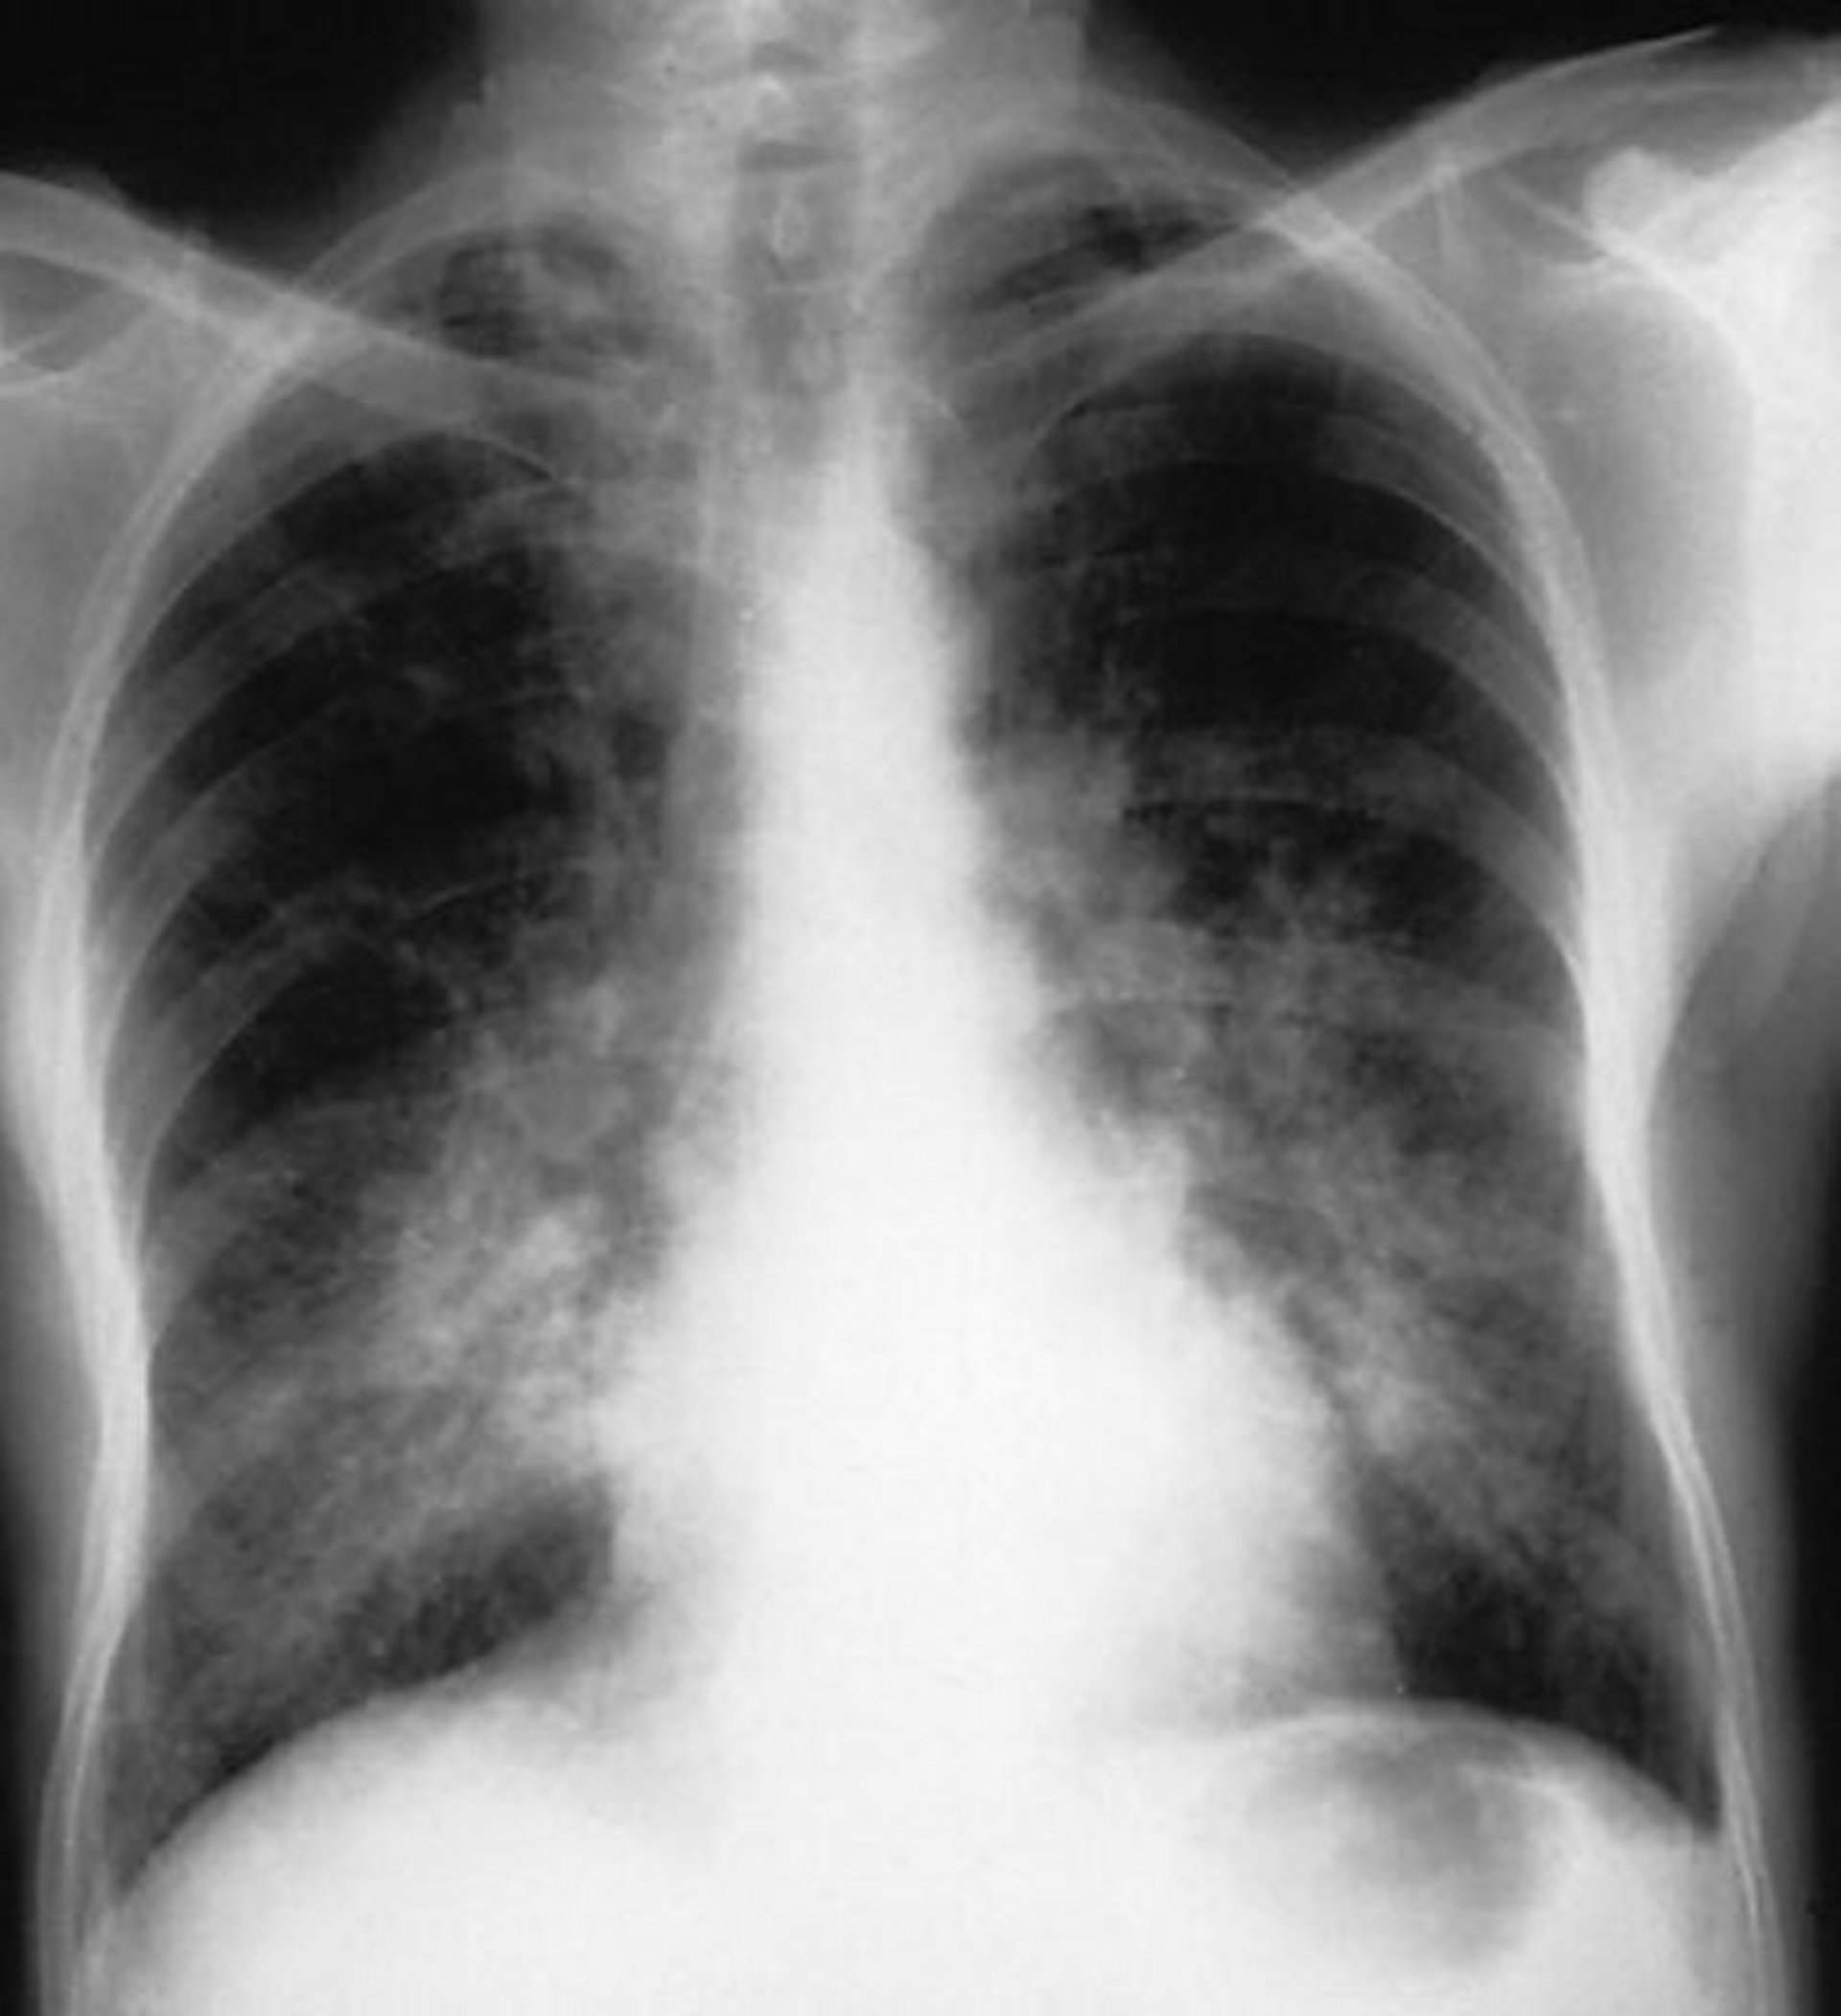

This chest radiograph shows bilateral alveolar opacities in a patient with alveolar hemorrhage.

By permission of the publisher. From Cohen A, Glassock R. In Atlas of Diseases of the Kidney: Glomerulonephritis and Vasculitis. Edited by R Schrier (series editor), RJ Glassock, and AH Cohen. Philadelphia, Current Medicine, 1999.